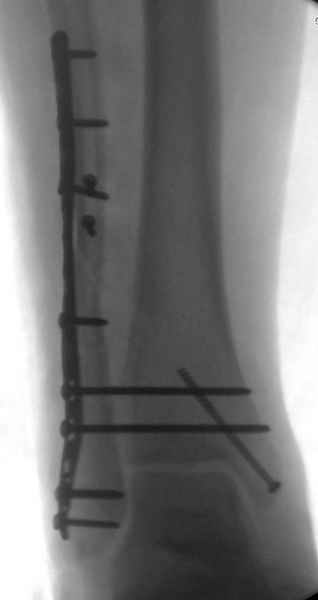

С мнением «провести позиционный межберцовый винт чуть ниже пластинки в положениий тыльного сгибания стопы» согласен, но я бы нагрузку начал через три недели и удаление шурупа можно провести через 6-8 недель.

Для облегчения удаления сломанных шурупов (случается часто) рекомендую фиксацию двумя 3.5мм кортикальными шурупами на 3 мм длиннее, тот же сломанный шуруп легко удаляется с медиальной стороны.

Здесь похожий случай трехнедельной давности, перелом почти сросся и была укорочена малоберцовая, на операции длину малоберцовой смогли восстановить только после того, когда проксимальнее пластины ввели шуруп и использовали его как толкатель, с помощбю дистракционого инструмента (lamina spreader).

Меньше всего волнует положение медиальной лодыжки - в любое время можно провести остео или реостеосинтез, при несращении можно просто резецировать без ущерба для движений в голеностопе. Здесь обошлись фиксацией одним 4 мм канюлированным шурупом.